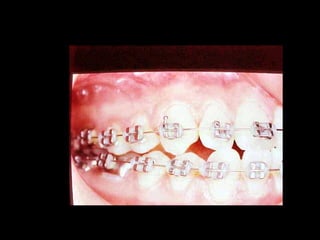

La paciente fue manejada iatrogénicamente por 5 años

Utilizando diferentes implementos ortodóncicos

La regla es clara: Laterognatias de más de 2º son quirúrgicas

La paciente fuemanejada iatrogénicamente por 5 años Utilizando diferentes implementos ortodóncicos La regla es clara: Laterognatias de más de 2º son quirúrgicas